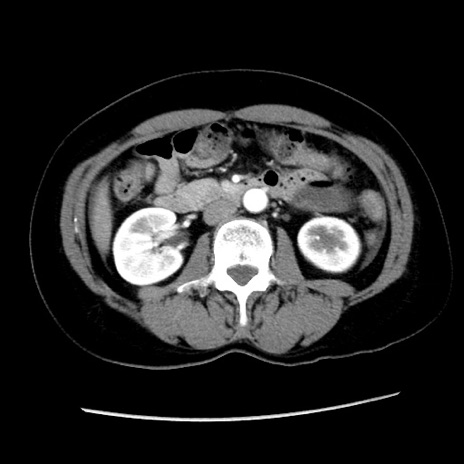

症例10(横断像)

【症例】 50歳代女性

【主訴】 腹痛

【現病歴】前日生レバーを食べた。今朝に排便あり。 昼前に突然発症の腹痛を生じ、当院救急外来を受診した。

【既往歴】 子宮筋腫にてで子宮全摘後

【身体所見】 意識清明、腹部:平坦、軟、下腹部やや左を中心に圧痛・反跳痛あり、筋性防御あり

【データ】WBC 7800、CRP 0.07